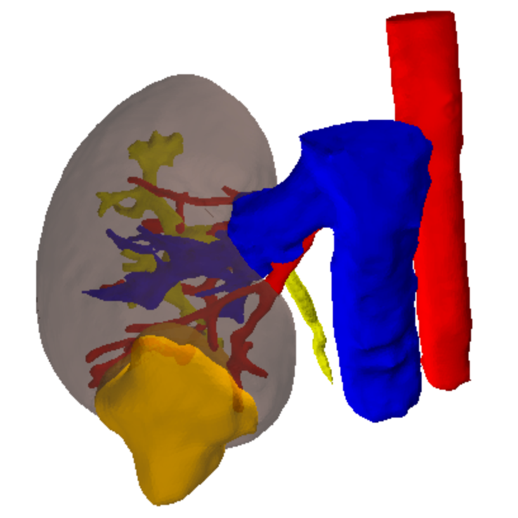

Patients diagnosed with an RCC usually get a CT-scan to assess the anatomy of the renal vasculature and the size and position of the tumour. This information, which consists of a stack of 2D-images as can be seen in Figure 2, is nowadays used to plan the clamping strategy. Using segmentation software, this 2D information can be segmented and 3D models can be generated, as shown in Figure 3. This results in a 3D visualisation of the kidney, the tumour, the blood supplying arteries and the relevant surrounding structures. Based on this information, surgeons can virtually test and optimize their approach using the planning tool software, e.g. giving estimations of the amount of viable and functional kidney tissue left after the procedure.